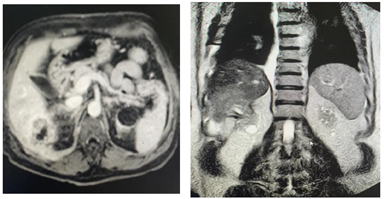

辅助检查:⑴肾脏彩超(2020年6月5日):双肾慢性损害性改变,左肾结石。双肾血流稍稀疏,血流参数正常;⑵肝胆胰脾彩超(2021年3月15日):脂肪肝(轻度)。胆囊壁毛糙。胰脾正常;⑶心脏彩超:左心增大。左室舒张功能减退。心包腔少量积液。彩超(腹部:含肝胆脾胰):肝内占位,性质待定,建议进一步检查;脂肪肝(轻度);胆囊壁胆固醇结晶;胆囊壁毛糙;胰脾未见明显异常;⑷胸部CT:右侧胸腔少量积液;心脏增大,心包少量积液;建议彩超检查;双肺间质性病变;⑸上腹部CT:肝右叶似见片状低密度影,建议行MRI检查,见图1。肝实质密度普遍减低,提示脂肪肝改变。胆囊管结石。上腹部MRI增强:右肾占位,考虑肾癌,并侵犯肝右叶及腹膜可能,见图2。双肾多发囊肿。肝S3段异常信号,考虑囊肿可能。右侧胸腔及心包积液;⑹心电图:窦性心律。完全性右束支传导阻滞。

患者血浆白蛋白、血糖、血脂、糖化血红蛋白、前白蛋白、蛋白分解代谢率均平稳,无营养状态差加重贫血因素;甲状旁腺激素、血钙、血磷均控制良好,无严重甲状旁腺功能亢进因素;血透超滤量2.7~3.2L/次,Kt/V值1.18~1.25,无血液透析不充分因素;患者否认促红细胞生成素不当保存情况,目前促红细胞生成素剂量(10000 U每周1次+3000 U两周1次),无促红细胞生成素使用不当及促红细胞生成素低反应性存在;患者白细胞、中性粒细胞、C-反应蛋白增高,较既往明显升高,考虑炎症状态加重导致,结合检查检验,无发热,无肺部感染、皮肤感染、泌尿系感染、胃肠炎等感染表现,进一步检查发现肝脏占位、肾脏占位,考虑肾脏肿瘤合并肝转移,但患者肿瘤标志物正常,无腹痛、腰痛、血尿等肿瘤相关临床症状。经与患者及家属充分沟通后,于2021年12月8日行腹腔镜下右肾癌根治术+腹腔镜下右肾周围粘连松解术,12月14日病理:右肾血管平滑肌脂肪瘤伴感染。